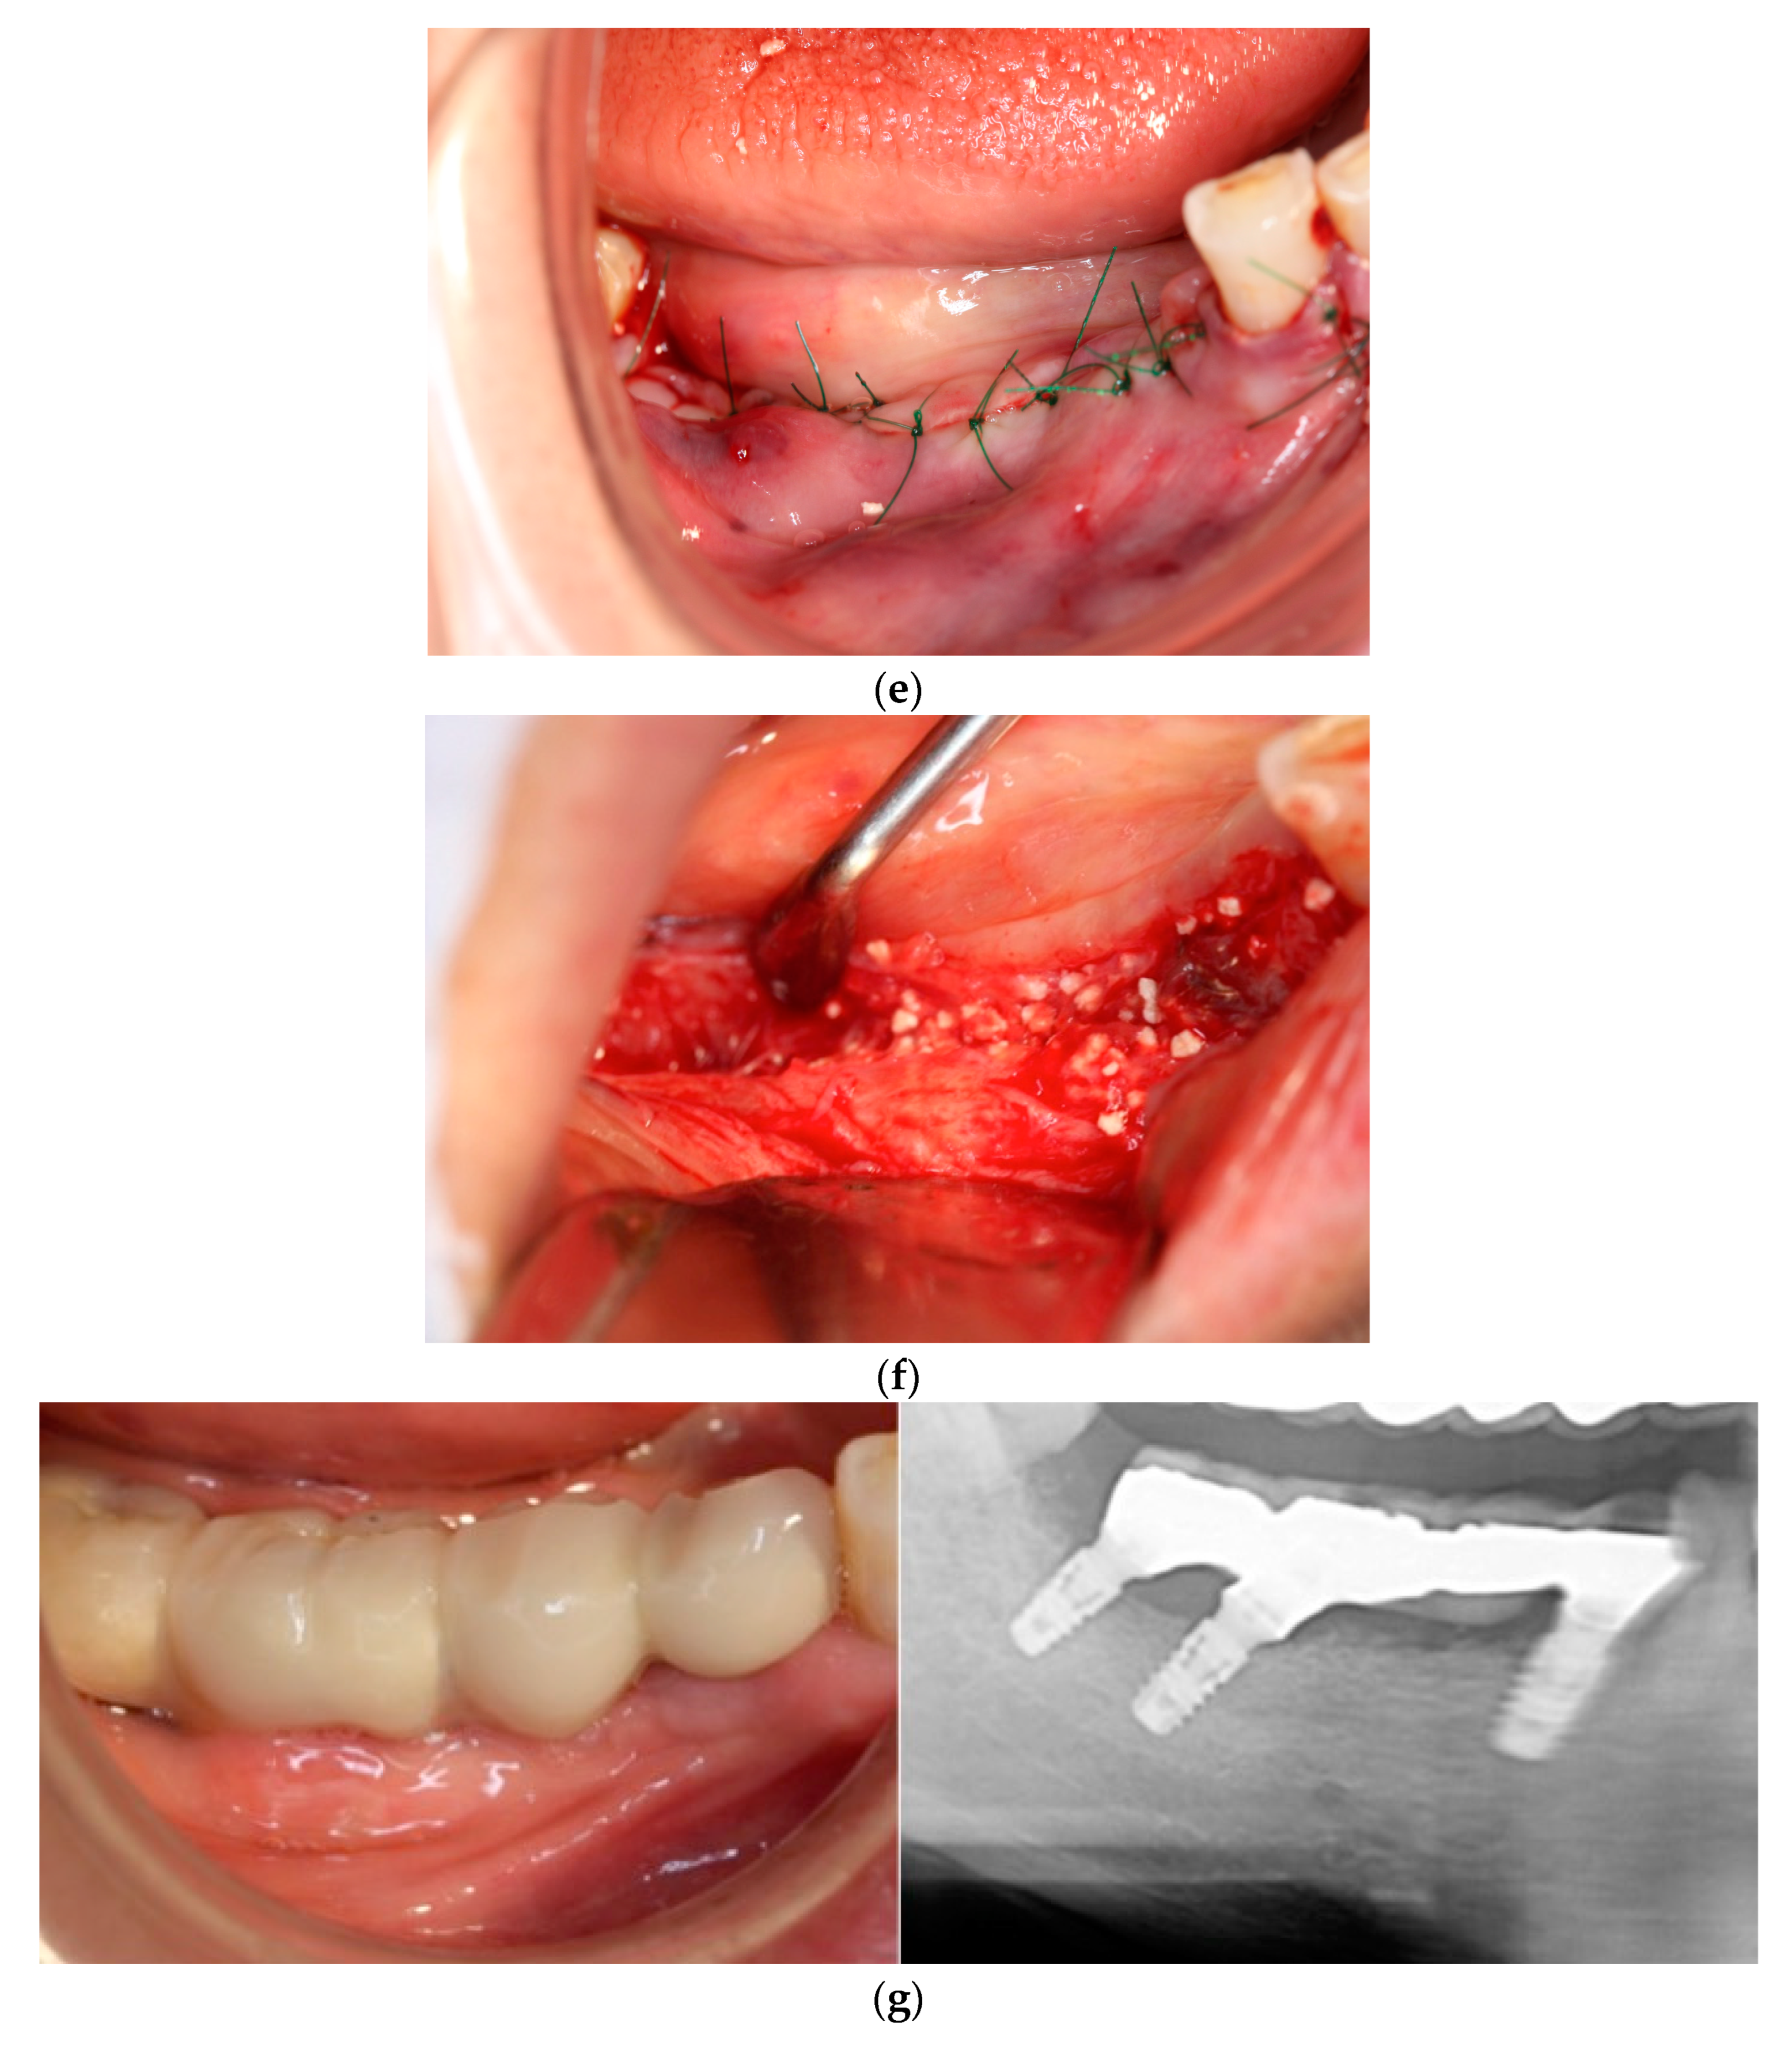

Figure 2. Case 2: Staged approach of implant placement following ridge preservation using carbonated apatite (CA; no membrane) immediately after fractured implant removal. (a) After flap reflection, a fractured and contaminated implant was observed. (b) Immediately after implant and granulation tissue removal. Residual bone volume was insufficient to achieve primary stabilization of simultaneous implant placement. (c) Bone graft. CA was placed into the implant removal socket. (d) After 5 months, at implant placement, the grafted CA was vertically and horizontally shrunk by external pressure. (e) Implant placement. The regenerated bone amount was not sufficient for the implant diameter. (f) Re-CA graft. CA was placed onto the exposed implant surface. (g) During uncovering. The new bone surrounding the implant was regenerated.

In each case, all implants ensured osseointegration during uncovering, and the peri-implant hard tissue was deemed stable. The results for Cases 2 and 4 are shown in Figure 2 and Figure 3, respectively. For SiRP, after 5 months of RP treatment, the implant was placed in the regenerated bone up to the height of the preserved alveolar ridge (Figure 2). In Case 4, the bone was hard and only 7 mm remained from the alveolar ridge to the inferior alveolar canal. The minimum length of the implant in this case was 8 mm, and to avoid postoperative complications such as paralysis, a safety margin of 2 mm was established, and the implant was placed after drilling for 5 mm. In addition, the molar area had significant vertical bone resorption and narrowing of the oral vestibule, and it was predicted that brushing would be difficult after the prosthesis. Therefore, the plan was to perform a vertical alveolar crest augmentation. Approximately 4.0 mm of vertical bone regeneration was achieved at implant 46 at 4 months following RA. Additionally, the exposed implant threads appeared to be completely covered with regenerated bone in the panoramic radiograph taken 24 months after prosthetic delivery (Figure 3).